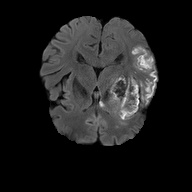

We conducted experiments on four brain imaging datasets: BraTS2017, BraTS2018, BraTS2019, and ISLES2022 [33, 34, 35, 36]. The BraTS datasets, developed for the MICCAI brain tumor segmentation challenge, contain 285, 285, and 335 labeled cases respectively, categorized into high-grade and low-grade gliomas. Each case includes 3D MRI scans from four modalities (T1, T2, FLAIR, T1c); we primarily used FLAIR. Preprocessing involved brain region cropping and intensity normalization. Dataset splits were 200/25/60 as train/val/test for BraTS2017 and BraTS2018, and 250/25/60 for BraTS2019. All experiments were conducted independently with models trained from scratch.

ISLES2022 focuses on stroke lesion segmentation in 3D multimodal MRI, with 250 cases including DWI, ADC, and FLAIR. We used DWI and split the dataset into 150 training, 40 validation, and 60 testing samples.

Quantitative Results. Tables 3–4 report results on BraTS2019, BraTS-2018, BraTS2017, and ISLES2022 datasets with limited labeled data (4% or 10%). On BraTS2019, our method outperformed most competitors in Dice, Jaccard, and 95HD, with a notable lead under the 4% setting, despite slightly lower ASD. On BraTS2018, it consistently surpassed all baselines, achieving nearly 2% higher Dice than the runner-up. It also achieved top performance on all metrics for BraTS2017, highlighting strong robustness and generalization. For ISLES2022 with 10% labeled data, our method significantly outperformed DAE-MT and closely matched the fully supervised model.

Qualitative Results. Figures 4, 3 present visual comparisons of the predicted segmentation results from our method and other baselines on the middle slice of the BraTS2018, BraTS2019, and ISLES2022 datasets. Our method demonstrates greater robustness and better coverage of the ground truth regions, particularly in areas where other methods fail to identify lesions and incorrectly classify them as background. Furthermore, our approach yields more accurate boundaries and preserves the overall shape of the target structures more effectively than competing methods.